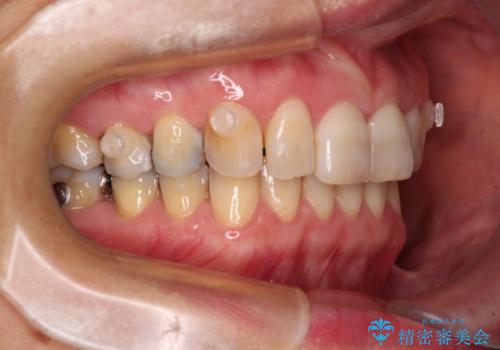

- 前歯のデコボコと上下正中のずれを気にして来院された患者様です。

下顎骨が骨格的にずれがあったため、しっかりと正中を合わせるとなるとワイヤー矯正が必要でしたが、マウスピース矯正を希望されたため、極力正中を合わせることを目標に、インビザラインにて矯正治療を行うこととしました。